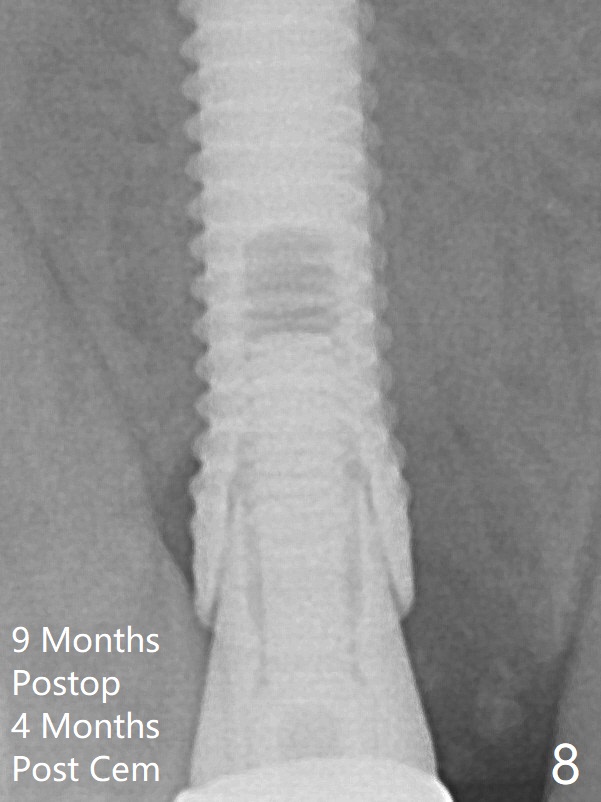

A final implant (3.8x15 mm) is placed with > 50 Ncm (Fig.4).  Before and after placement of a 4.5x5(3) mm abutment, Vera graft is placed in the remaining socket space (mainly buccal, Fig.5 *).  As routine, an immediate provisional is fabricated with occlusal clearance.  The bone graft appears to remain in place 4.5 months postop (Fig.7).  The bone density around the coronal portion of the implant increases 9 months postop (4 months post cementation, Fig.8).